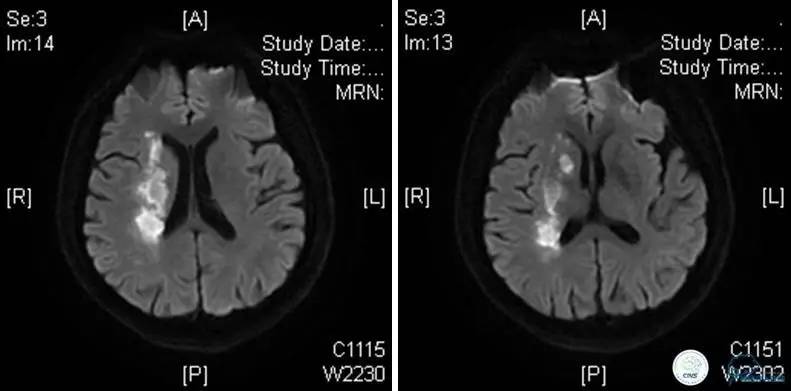

患者:49岁男性,左侧偏瘫1个月,药物治疗、康复训练效果不好,转我院,肌力0~1级。

core-clilnical明显不匹配,是介入开通的合适患者。

术后即刻和6天后CT,患者无明显临床症状。